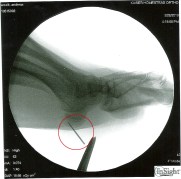

Tags darauf finde ich mich in der Minor Injury Clinic in Mountain View ein. Äußerlich ist keine Wunde mehr zu erkennen. Und so schickt mich Dr. George Greenwald zum Röntgen. Irgendwie komme ich mir fast schon vor wie ein Hypochonder. Doch als sich George die Röntgenbilder ansieht, weiß ich schlagartig: uh-oh, schlechte Nachrichten.

Ein Drittel der Nadel steckt tief in meinem Fuß. Das sind 1,5 Zentimeter Metall. Um sie zu entfernen, muss man zunächst allerdings im wahrsten Sinne des Wortes die Nadel im Heuhaufen finden.

Am Ende werde ich unter einem Röntgenapparat operiert. Langsam schneidet sich Dr. Smith zu den Zielkoordinaten vor. Nach 25 Minuten gelingt es ihm, die Nadel zu entfernen. Die Wunde wird zugenäht, mein Fuß dick umwickelt, und ich fahre nach Hause. Die nächsten 3 Wochen bin ich lahmgelegt.